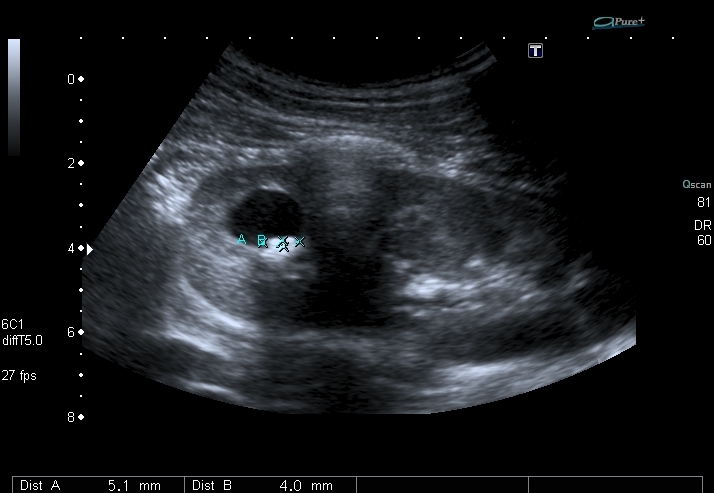

Мальчик 14 лет, на плановой госпитализации, выставлен хронический пиелонефрит.

Артефакт цветного твинклинга

Ранее на КТ - Киста почки с кальцинатами.

Полость в врехнем полюсе, но на Фрейли не похоже - нет сосуда на ЦДК под полостью. Была мысль о дивертикуле чашечки, будем дообследовать путём экскреторной урогфии, изображения выложу.KapustinSV писал(а):Cлева "голова" или справа?

Мальчика выписали без рентгенологического исследования. Будем обходиться УЗИ. Почему это не может быть кистой с конкрементами? Формирование конкрементов в кисте менее вероятно, чем в дивертикуле чашечки или в расширенной чашечке при синроме Фрейли. Но полость уж больно круглая, да и связи с ЧЛС и конфликта с интраренальным сосудом сколько не смотрел, я не увидел.